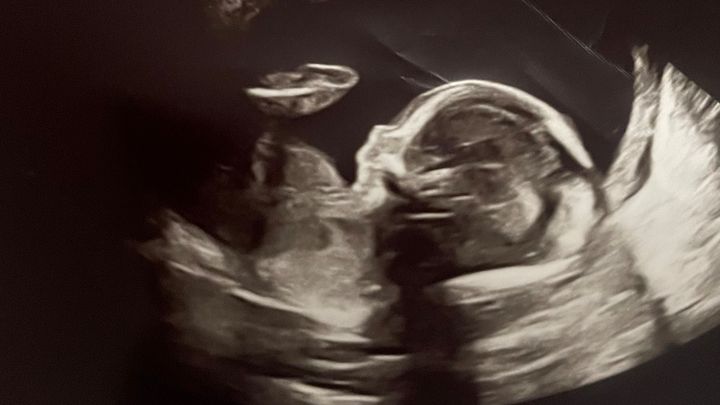

At just 20 weeks into her pregnancy with their third son, my sister and brother-in-law received news that turned their world upside down – she has been diagnosed with both placenta previa and placenta increta/precreta

(They are hyperlinked so that you can see more details of these conditions.) These are life threatening conditions to both my sister and her unborn baby that require expert surgical and medical care. Placenta previa can lead to dangerous bleeding, while placenta increta / precreta brings the risk of life-threatening hemorrhaging during childbirth due to the placenta's abnormal growth and attachment to her vital organs. The placenta has now grown completely though the uterus wall and is laying on the bladder. It’s only a matter of time before the placenta invades her bladder and other organs. (As a result, Ariel will have to endure a full hysterectomy immediately following the birth of her baby.)

The good news is that a team of highly regarded experts who specialize in these conditions work at the highly specialized medical facility at St. Luke’s Medical Center in Denver, a two-hour journey from their home. The bad news is that for her, and the baby’s, safety she is an inpatient and must stay at the hospital so that the highly experienced surgeons and medical staff can observe, and care for her immediately in case of hemorrhaging prior to delivery, (a very real threat). The doctors want to get her to at least 34 weeks to give the baby the best chance of survival.